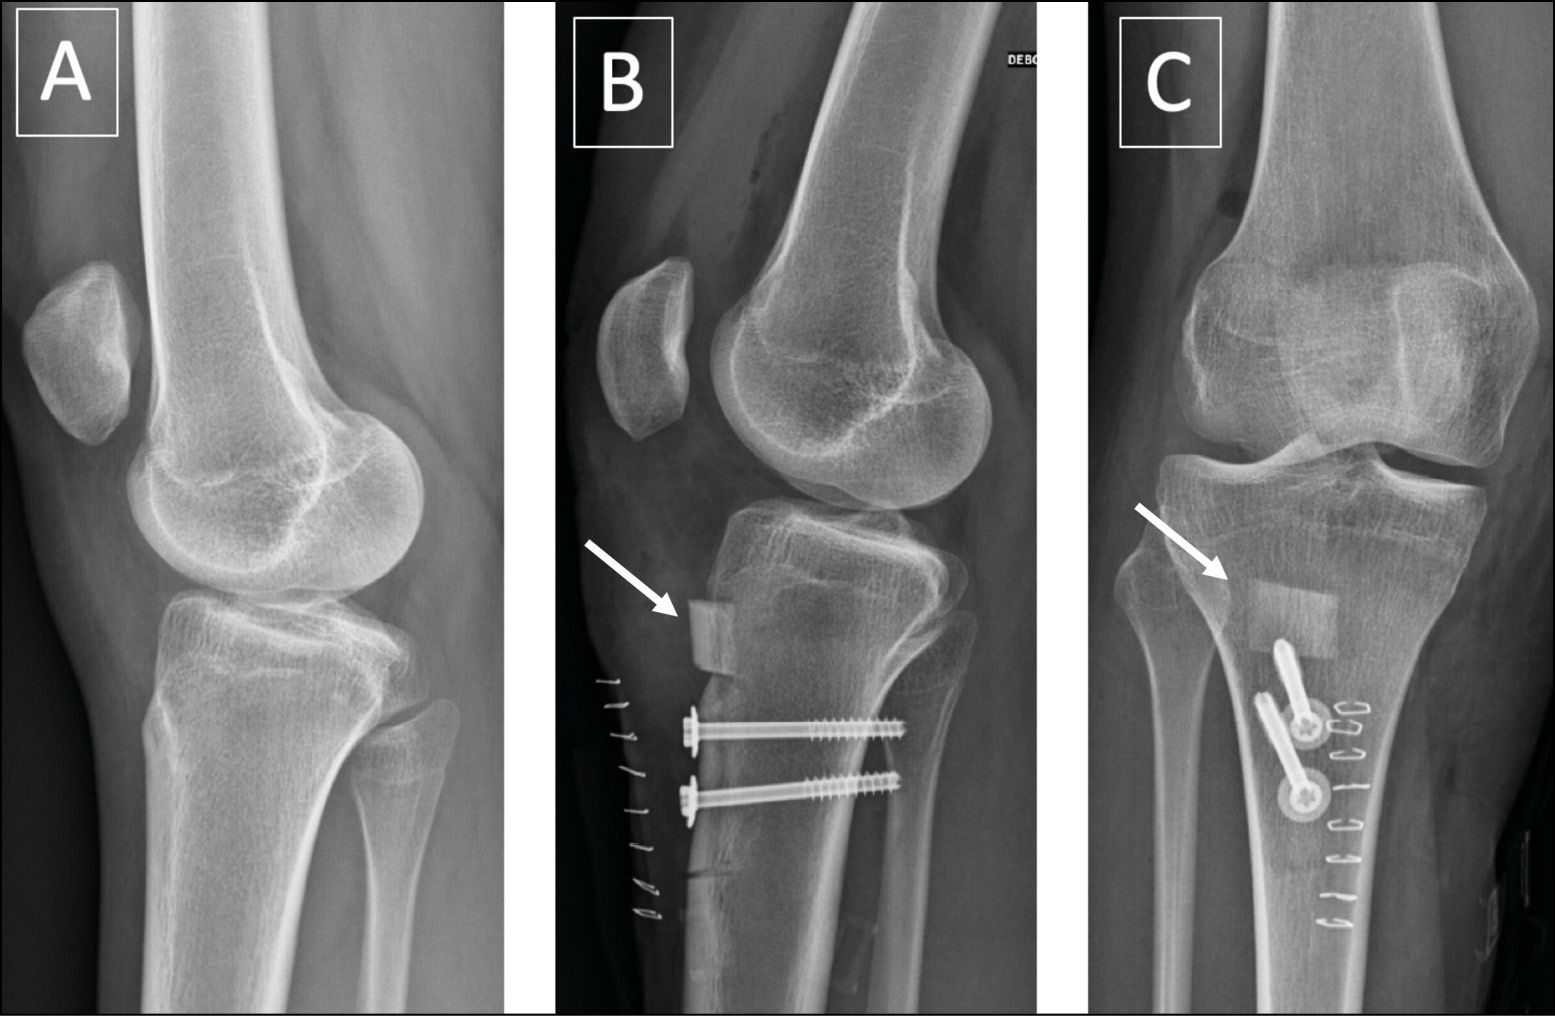

The clinical contributions in this issue span key domains of knee and patellofemoral pathology. The management of idiopathic patellofemoral pain is addressed alongside surgical options for chronic quadriceps rupture repair, contrasting the Chambat technique with the sardine tin technique. Anterior tibial tuberosity distalization osteotomy is examined as a corrective strategy for painful patella alta. A historical perspective traces the evolution from resection arthroplasty to partial knee replacements, contextualizing contemporary implant selection within a broader clinical legacy.